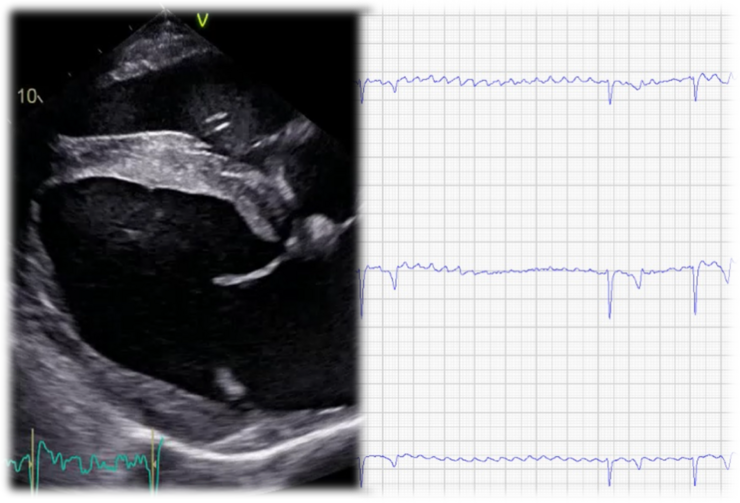

Herzkrankheiten

Herzrhythmusstörungen oder Herznebengeräusche fallen häufig bei Routineuntersuchungen auf. Oft stellt sich im Anschluss die Frage, ob die zugrundeliegende Erkrankung das Pferd im Laufe des Lebens beeinträchtigen kann. Um den Schweregrad einer solchen Erkrankung zu beurteilen ist spezialisierte, weiterführende Diagnostik notwendig.

Eine Herzuntersuchung kann je nach Indikation ein bis zwei Tage dauern und beinhaltet eine klinische Untersuchung, einen Herzultraschall sowie nach Bedarf ein Langzeit- und Belastungs-EKG. Die Beurteilung des reiterlichen Risikos erfordert in der Regel eine vollumfängliche Untersuchung.

Vorhofflimmern ist die häufigste Herzrhythmusstörung beim Pferd und kann mit einer Leistungsschwäche einhergehen. Wir bieten als derzeit einer von wenigen Kliniken in Europa die risikoarme Therapie mittels transvenöser elektrischer Kardioversion (TVEC) an.

Vorhofflimmern und Transvenöse Elektrische Kardioversion (TVEC)

Vorhofflimmern beim Pferd – moderne Diagnostik und sichere Therapie mittels TVEC

Vorhofflimmern ist die häufigste klinisch relevante Herzrhythmusstörung beim Pferd und kann die Leistungsfähigkeit deutlich beeinträchtigen. In unserer Klinik werden betroffene Pferde standardisiert kardiologisch untersucht. Liegt keine Gegenanzeige vor, erfolgt die Behandlung mittels Transvenöser Elektrischer Kardioversion (TVEC) – einer etablierten und sehr erfolgreichen Therapiemethode.